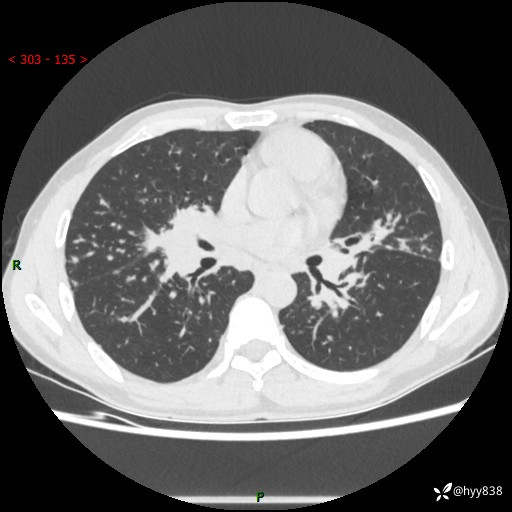

中年男性,咳嗽咳痰1月余。细看:肺、肺门、气管,貌似都有问题---(有结果)

现病史:患者于1个月前受凉后出现间断性咳嗽,伴白色泡沫样痰,无发热寒战、咯血、胸痛胸闷、恶心呕吐、呼吸困难等特殊不适,起初未予特殊处理,后患者就诊当地中医医院,查胸部CT提示支气管炎并双肺感染性病变,经抗感染(哌拉西林舒巴坦),止咳化痰(溴己新、三拗片)等治疗后,患者自诉咳嗽咳痰症状较前缓解,未诉发热等其他特殊不适,近期复查CT提示“肺部感染灶未见消退,双侧肺门增大,双肺散在小结节”,今为求进一步诊治,前来我院就诊,门诊以“肺部感染”收住入院。 患者自起病来精神、食欲、睡眠尚可,大小便正常,体力、体重无明显变化。

胸部CT平扫+增强(两期)